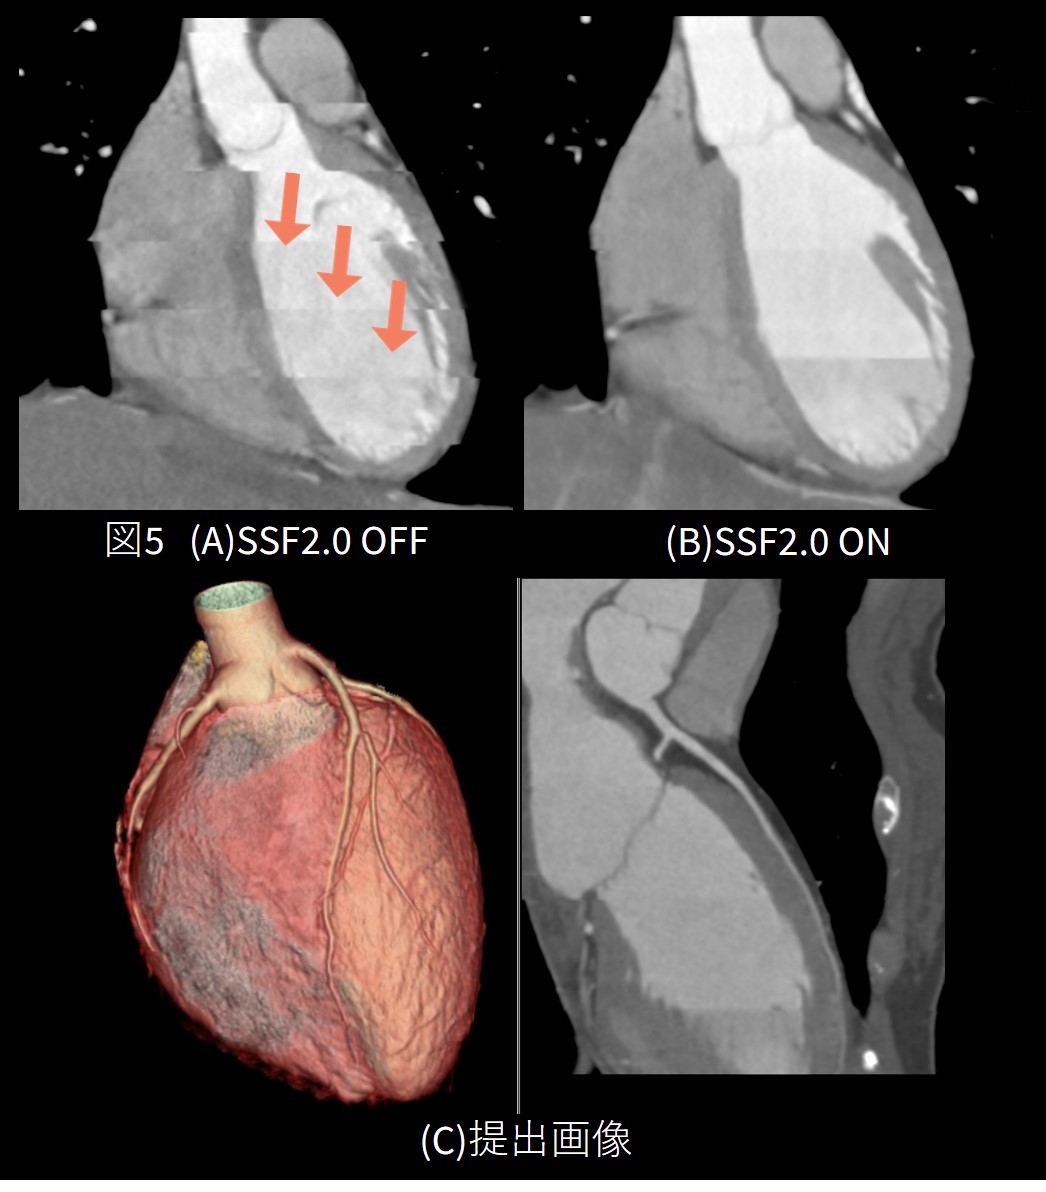

心拍は62BPM程度で安定していましたが、造影中に息止めがうまくできなかった症例です。図5(A)のMPR像を見ると左図の矢印のような多数のバンディングアーチファクトが発生しています。

初見の印象では正直なところ良好な制止画像が得られないのではないかと思いました。冠動脈の動きはSSF2にまかせ、心臓自体の動きが一番少ない位相(心位相80%)を、なるべく少ないデータ量で再構成するなどの工夫をしました。

その結果、バンディングアーチファクトを解消し臨床で評価可能な画像を提出することができました。

また冠動脈解析時にもワークステーションのバンディング補正機能(Intelligent Boundary Registration: IBR)を使用し、図5(C)のように途切れのないCPR像を提出することができました。